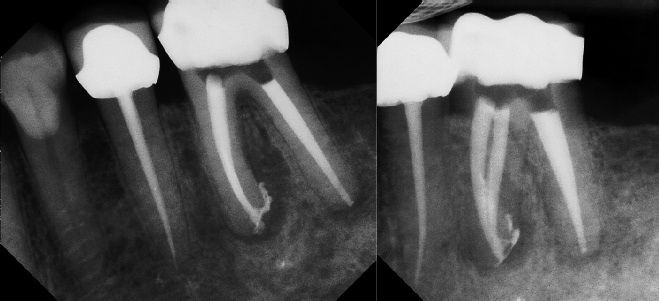

Root Canal Retreatment - Meriden 8 mos. recall Post-op Pre-op